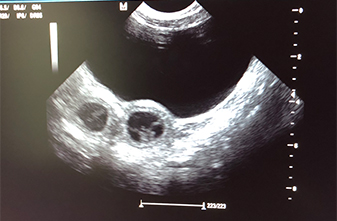

Heute war also der Tag der Tage. Der Tag an dem man Gewissheit bekommt, ob die Hündin aufgenommen hat oder nicht.

Auch wenn Enjas Verhalten zu 100% für eine Trächtigkeit spricht, so wollten wir es gerne

von unserer Tierärztin Heike Trei absegnen lassen. :-)

Beim Ultraschall wurden auf Anhieb einige Fruchtanlagen gesichtet. Die genaue Anzahl wollte ich aber nicht wissen.... ein bisschen Spannung soll uns und den Welpeninteressenten schon noch in den kommenden Wochen erhalten bleiben. ;-) |

Wir freuen uns einfach riesig darüber, dass bald kleine G-Bagaluten den Bagalutenhof besetzen werden.

Bis dato werden wir Enja weiterhin fit halten und auf unser Essen aufpassen. :-)